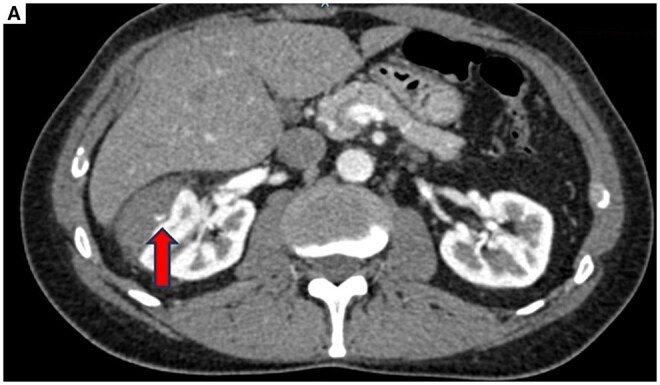

选择性栓塞是稳定患者外伤性肾假性动脉瘤(PSA)的首选治疗方法。n -丁基-2-氰基丙烯酸酯(NBCA)是一种常用的栓塞剂,用于栓塞周围病变。正丁基-2-氰基丙烯酸酯是应用最广泛的栓子材料之一,因为它易于制备,作用迅速,成本效益高。然而,在变得自信并能够安全地使用它之前,它的使用需要一个学习曲线。我们描述了一个病例的肾创伤性PSA栓塞没有明确的术前ct证据动脉-盏瘘,其中NBCA在肾盂的迁移发生在手术过程中。我们报告成功的多学科管理的并发症。

Selective embolization is the treatment of choice for traumatic renal pseudoaneurysm (PSA) in stable patients. N-Butyl-2-cyanoacrilate (NBCA) is an embolic agent frequently used to embolize peripheral lesions. N-Butyl-2-cyanoacrilate is one of the most widely used embolic materials because it is easy to prepare, it acts quickly and is highly cost-effective. Its use, however, requires a learning curve before becoming confident and being able to handle it safely. We describe a case of embolization of a renal traumatic PSA without clear pre-procedural CT-evidence of artero-calyx fistula in which the migration of NBCA in the renal pelvis occurred during the procedure. We report the successful multidisciplinary management of this complication.